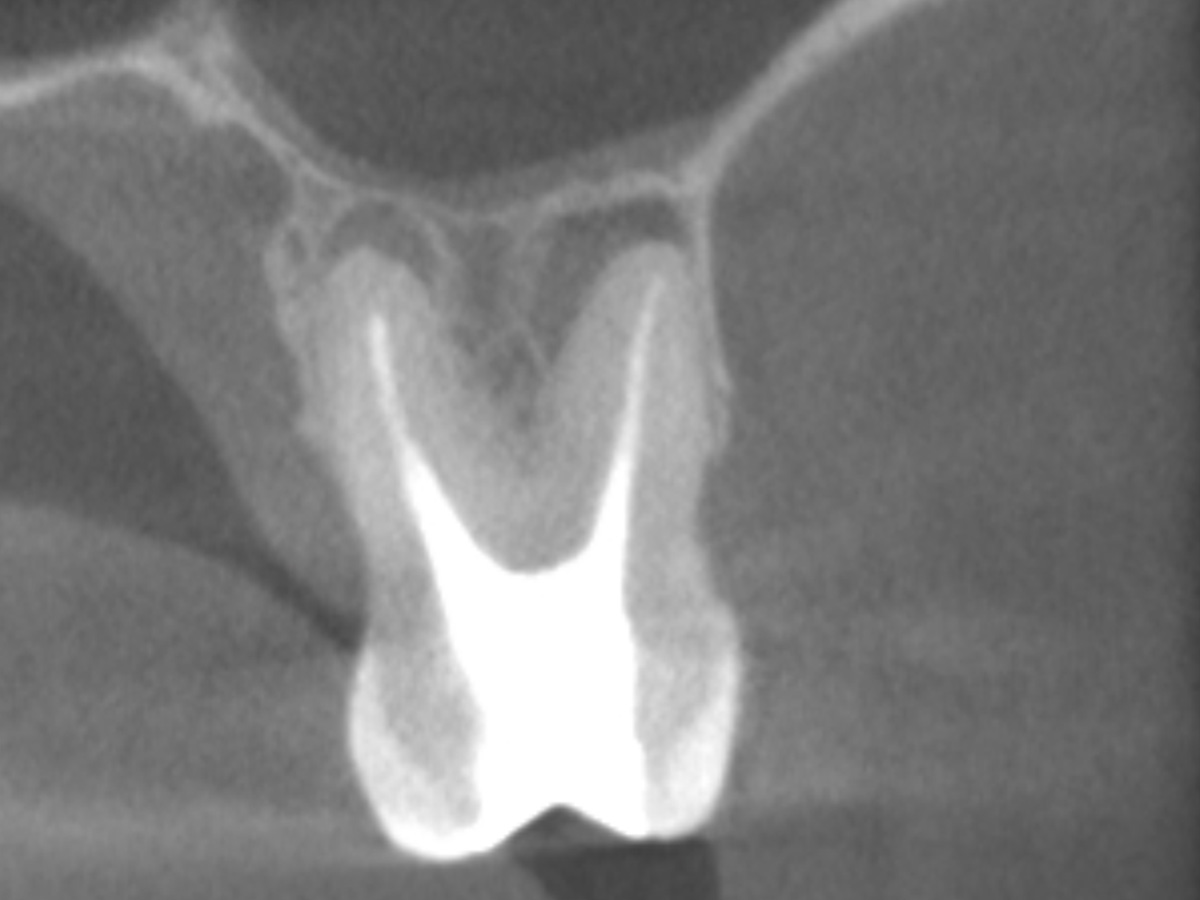

Der Patient stellte sich mit Aufbissschmerzen vor, wobei die klinische und röntgenologische Untersuchung eine symptomatische apikale Parodontitis an einem bereits wurzelkanalbehandelten Zahn 26 ergab. Die DVT-Aufnahme deutete auf einen unbehandelten zusätzlichen Kanal in der mesio-bukkalen Wurzel hin. Die Darstellung und Behandlung des mb2s sowie die Revision der bereits behandelten Kanäle erfolgte mit dem XP-endo® Rise Shaper bei einer hohen Umdrehungszahl von 2.500rpm.

DVT koronal